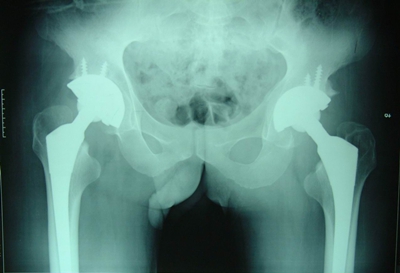

图2.双髋关节一次性置换术后